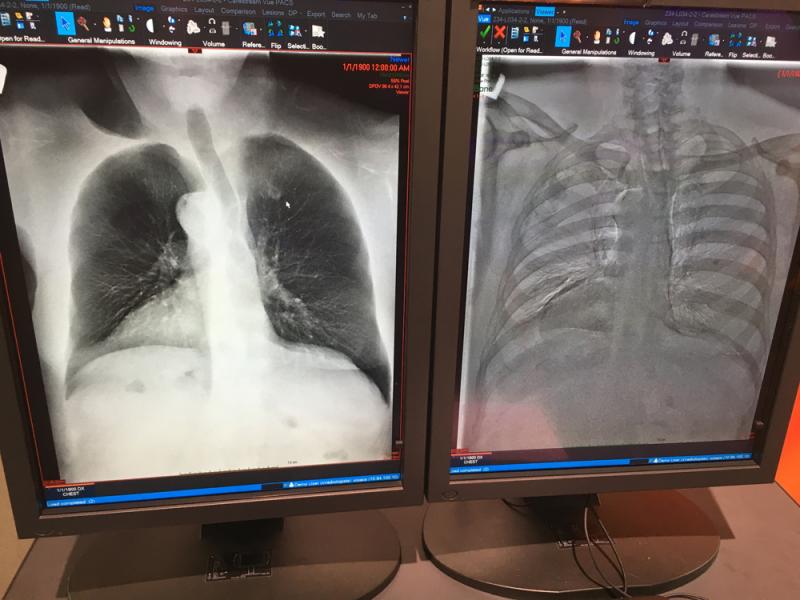

This is a lung X-ray reviewed automatically by artificial intelligence (AI) to identify a collapsed lung (pneumothorax) in the color coded area. This AI app from Lunit is awaiting final FDA review and in planned to be integrated into several vendors' mobile digital radiography (DR) systems. Fujifilm showed this software integrated as a work-in-progress into its mobile X-ray system at RSNA 2019. GE Healthcare has its own version of this software for its mobile r=ray systems that gained FDA in 2019.

Here are images of some of the newest new medical imaging technologies displayed on the expo floor at the Radiological Society of North America (RSNA) 2019 meeting. Use the slider images below to see the photos.